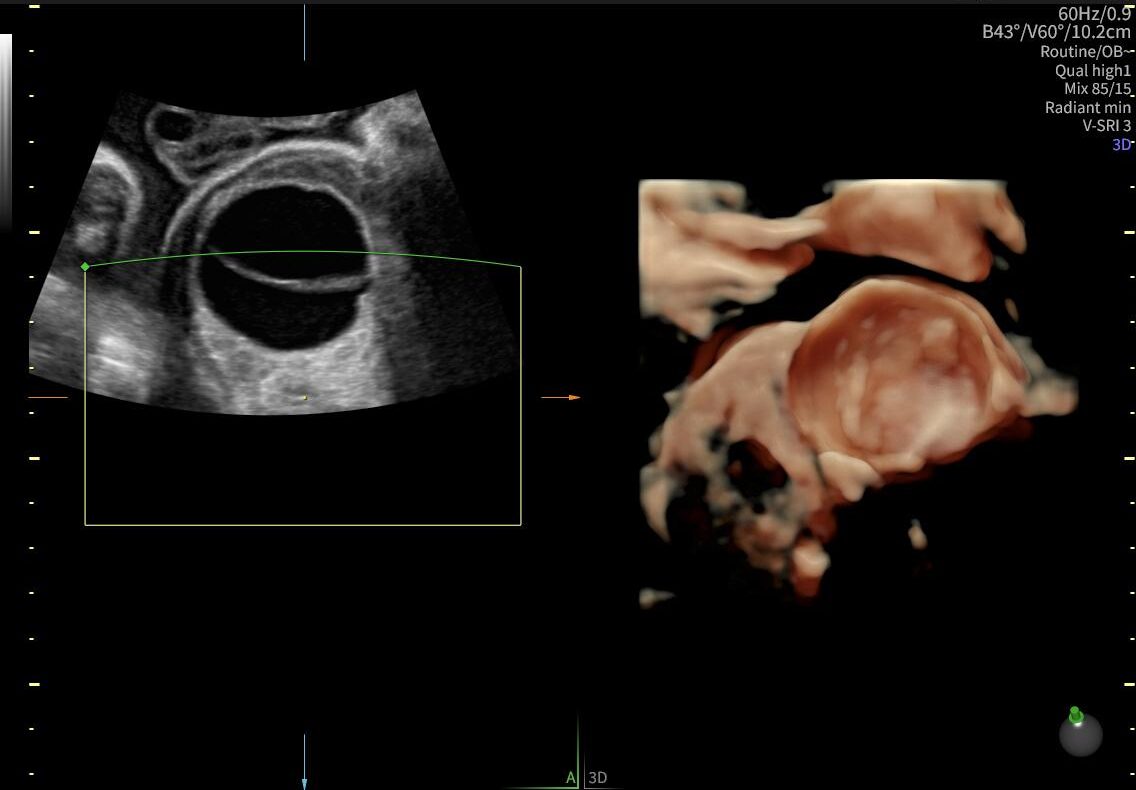

La ecografía ginecológica es un estudio por imágenes no invasivo que permite evaluar de forma precisa el útero, los ovarios y el sistema reproductor femenino. Es una herramienta fundamental para la detección temprana de alteraciones ginecológicas, el seguimiento de tratamientos y los controles preventivos.

En OBGYN Perú, realizamos ecografías ginecológicas con equipos de alta resolución, garantizando resultados confiables y una atención médica especializada.